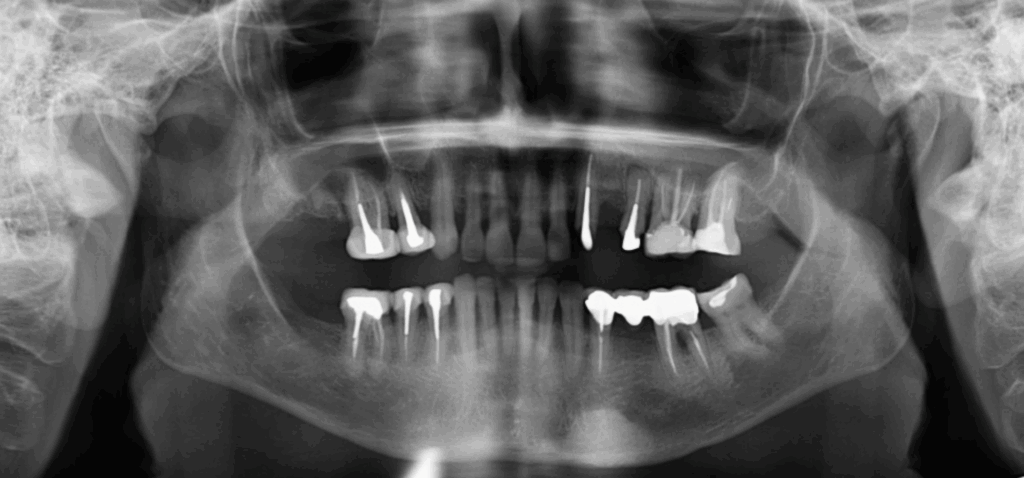

Paciente femenino de 69 años acude al Instituto para realizar una tomografía con fines de rehabilitación oral, a la evaluación de la radiografía panorámica se observa aplanamiento de ambos cóndilos mandibulares, neumatización de ambos senos maxilares, asimismo se observa la presencia de una imagen radiopaca de densidad ósea, de forma ovalada que se proyecta en cuerpo

mandibular del lado izquierdo y sobre el reborde basal. También se puede observar el edentulismo parcial de la paciente, remanente radicular de la pieza 17, múltiples piezas dentarias con corona, espigo y obturación de conductos, la pieza 25 además presenta proceso osteolítico periapical y la pieza 46 presenta proceso osteolítico interradicular y osteítis condensante circundante.

A la evaluación de la tomografía volumétrica de campo 10 x 10 se observa la presencia de la misma imagen hiperdensa a nivel mandibular del lado izquierdo y por vestibular de limites definidos y base pediculada a la altura de las piezas 33 y 34 y muy cerca al conducto dentario inferior compatible con osteoma mandibular.